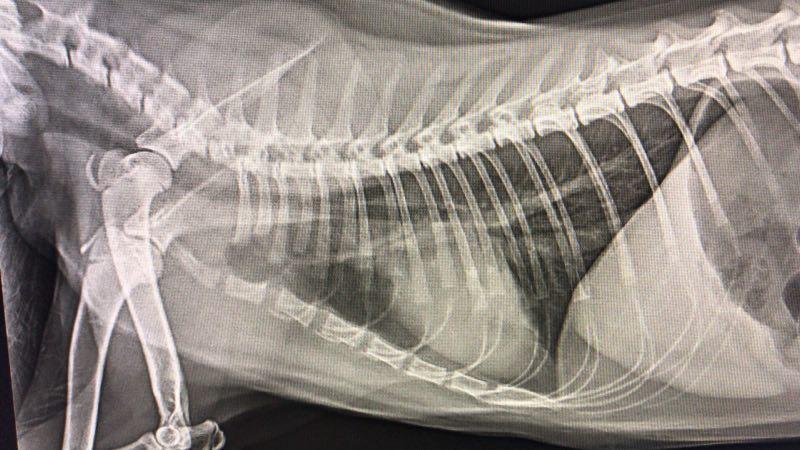

猫咪肺炎的检查方法

一般给猫咪做胸部X光检查和血常规来确定猫咪是否肺炎。也可通过超声波来检测肺部的感染。

▲未感染肺炎的x光